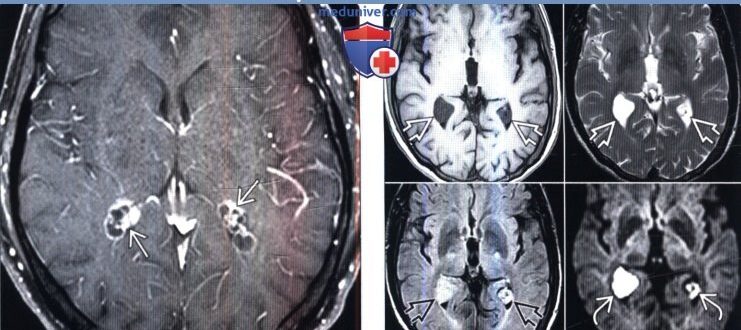

Двусторонние кисты хороидных сплетений боковых желудочков мозга

Кисты сосудистых сплетений головного мозга у плода: причины, последствия Второй плановый ультразвуковой скрининг при беременности направлен на выявление аномалий эмбрионального развития. Кисты сосудистых сплетений головного мозга у плода…